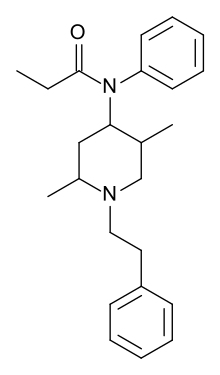

Anilidopiperidines

Phenylpiperidines